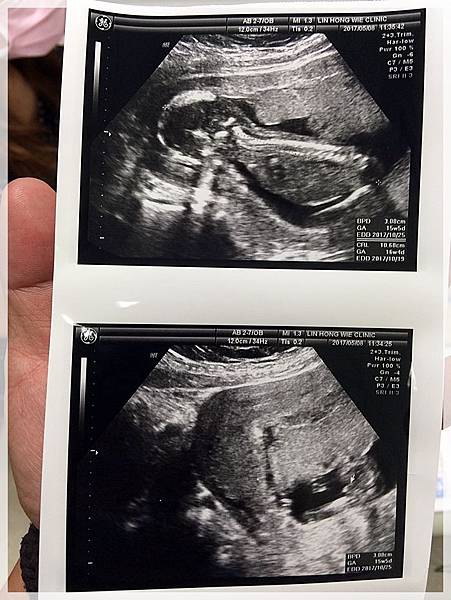

2017.05.08 紜紜6y06m02d 妞妞4y03m29d

今天我們去產檢,來去看樂樂囉![]()

樂樂有乖乖的長大...

醫生叔叔也說確定樂樂是男生不是在下面比讚喔![]()